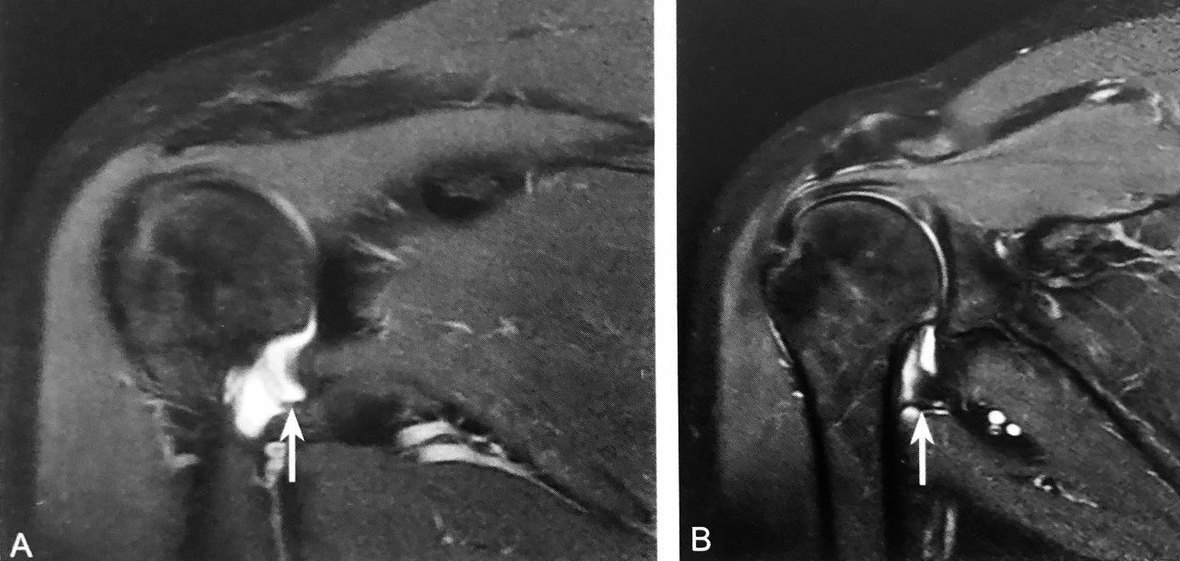

双肩锁关节征:A 图冠状位压脂 PD 序列显示,肩峰关节面下可见游离的条状、未融合肩缝小骨(箭头),肩锁关节囊积液,伴肩峰下-三角肌下滑囊积液,同时可见冈上肌肌腱撕裂(三角);B 图矢状位压脂 PD 序列显示:未融合肩峰小骨与肩峰关节面、肩锁关节形成双肩锁关节,肩锁关节囊积液,伴肩峰下-三角肌下滑囊积液(箭头)

判读要点:

1、在肩关节 MRI 冠状位或矢状位观察;

2、须同一层面同时观察到肩锁关节及肩峰小骨;

3、注意双肩峰关节征与第二肩锁关节区别;

4、观察肩峰小骨是否稳定,如不稳定,是否与邻近软组织产生撞击,此时应注意观察是否伴有周围积液、水肿、肩锁关节损伤及肩袖损伤。